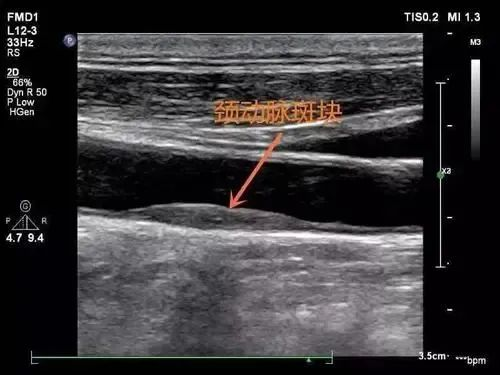

通过超声检查可以观察颈动脉内膜是否有增厚,是否有斑块形成,斑块大小、部位及斑块表面是否有溃疡,是否有血管狭窄及狭窄程度;通过测量颈动脉血流速度,间接估计颈动脉狭窄程度。